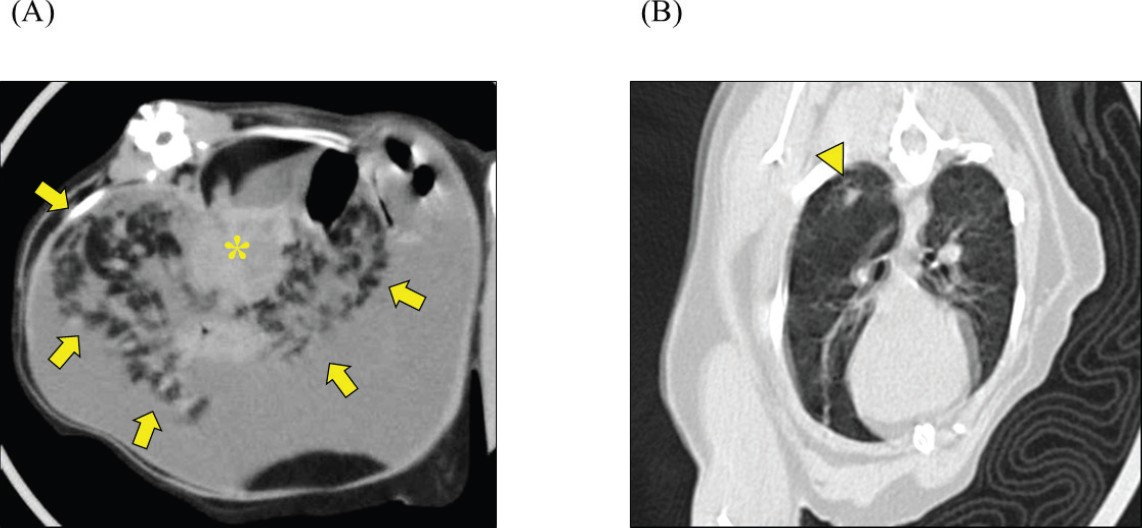

初次就诊后的第12天,进行了非镇静CT。未使用麻醉,将患者固定在亚克力笼中(CT胶囊)。CT显示胰腺呈肿瘤样增大,腹膜背侧不规则散在结节聚集,右肺下叶呈磨玻璃样改变(下图)。由于未进行血管造影,无法评估血管特征和软组织肿块的更详细鉴别。

↑ CT扫描。显示了(A)上腹部和(B)胸部的横断面CT图像。肠系膜脂肪显示出以增大且呈肿瘤样胰腺(*)为中心的散在结节,且结节轮廓不规则(箭头)。右肺下叶观察到磨玻璃样改变(三角)。